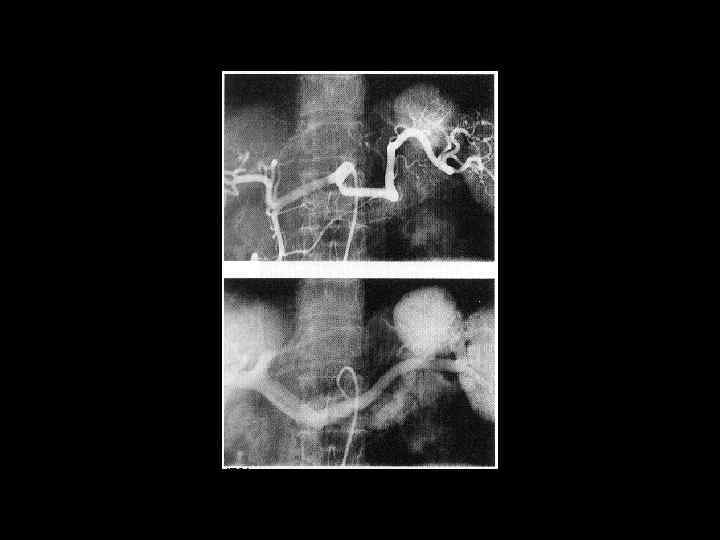

АКТУАЛЬНЫЕ ВОПРОСЫ РЕНТГЕНОЛОГИИ ЛУЧЕВАЯ ДИАГНОСТИКА ЗАБОЛЕВАНИЙ СЕЛЕЗЕНКИ Спленомегалия: Причины - Заболевания системы крови (гемолитические анемии, острые лейкозы, хронический миелоидный лейкоз, злокачественные лимфомы) - портальный цирроз печени - тромбоз селезеночной вены

АКТУАЛЬНЫЕ ВОПРОСЫ РЕНТГЕНОЛОГИИ ЛУЧЕВАЯ ДИАГНОСТИКА ЗАБОЛЕВАНИЙ СЕЛЕЗЕНКИ Травма и инфаркт селезенки